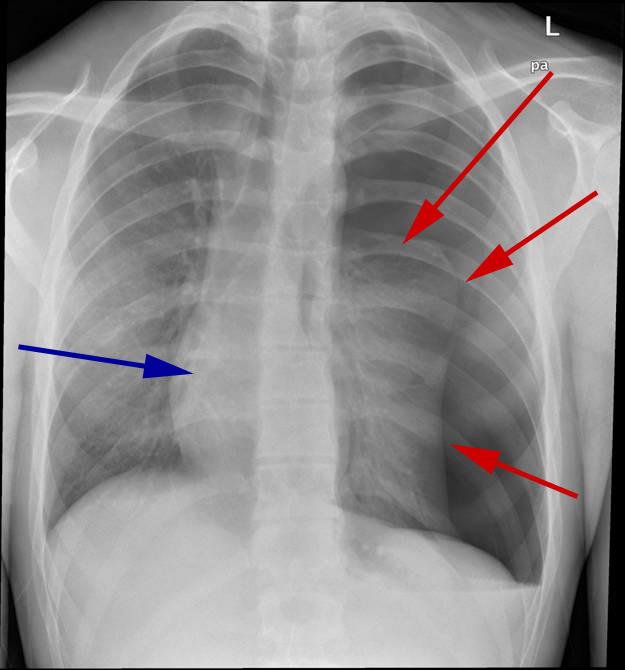

Røntgenbillede af thorax viser, at den venstre lunge er klappet delvist sammen (røde pile viser grænsen), og hjertet (blå pil) er forskudt over mod højre.